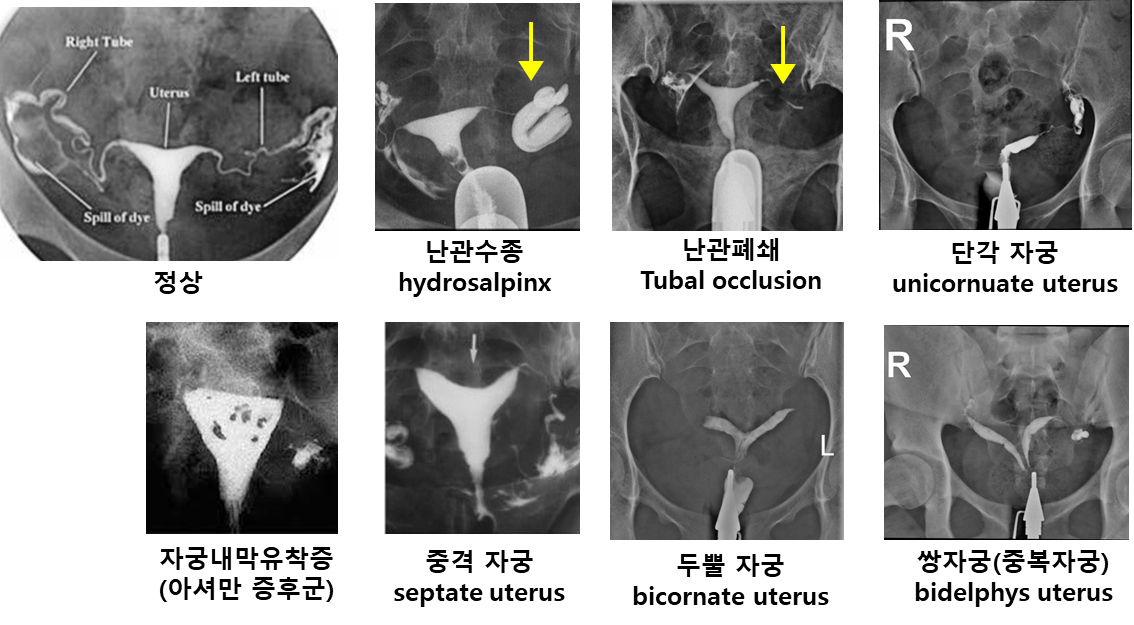

난관 평가

• 자궁 난관 조영술 (월경 주기 9-12일)

: 월경이 끝난 직후에 시행, 난관 폐쇄나 비정상 자궁 구조 등을 확인할 수 있음

(PID가 진단되거나, 이미 난관수종이 있다고 알려진 환자에서는 시행하지 않음)

• 정상 소견

• 조영제가 양쪽 나팔관의 말단에서 복강 내로 spill 되며, 정상 자궁 내강이 확인

• 비정상 소견

• 난관 폐쇄 : 나팔관 말단에서 조영제의 spill 이 보이지 않고, 난관이 비정상적으로 확장되어 난관 수종을 보이는 경우도 있음

• 비정상 자궁강 : 자궁내막 유착증, 자궁 내막 근종/폴립, 자궁 기형 등을 확인